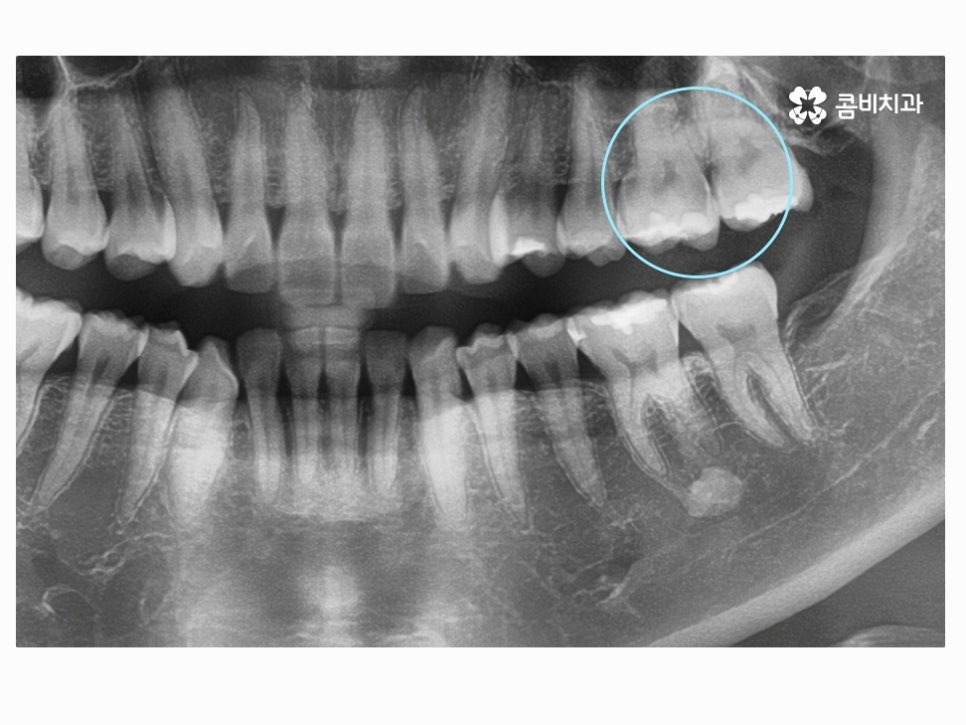

이미 과거에 충치 치료를 했다고 하더라도 치료 후 수년간의

시간이 흐르면 치료에 쓰인 접착제가 녹거나 치료재와

치아 사이의 공간이 발생하여 내부 충치로 이어지는 경우가 있는데요.

충치를 인레이 혹은 크라운 치료로 이미 했더라도 개인에

따라 식습관, 생활환경이 다르겠지만 약 7~10년 이상 사용을

했다면 교체가 필요할 수 있기 때문에 주기적으로 검진하면서

이러한 내부 충치에 대한 예방을 잘 하실 필요가 있어요.

나이가 들수록 이처럼 이미 충치 치료를 했었던 치아 안에서

내부 충치가 발견되는 사례가 많은데 명동치과 주기적으로

검진을 잘 했다면 이러한 내부 충치를 빠르게 발견하고

치아 손상을 줄일 수 있기 때문에 치료를 했던 치아라도

방심하지 않고 지속적으로 관심을 가질 필요가 있어요.